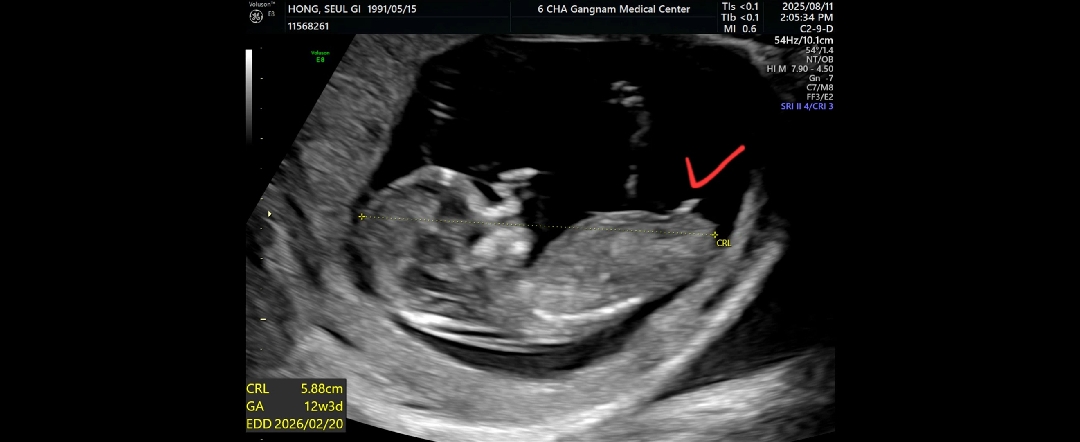

결과적으로 딸이었습니다 ㅎㅎㅎ

2026년 2월 베동

각도법 궁금쓰

딸일까여 아들일까여 ㅎㅎㅎ AI에 물어보니 챗지피티는 아들이라하고, 제미나이는 딸이라네요 하하하하